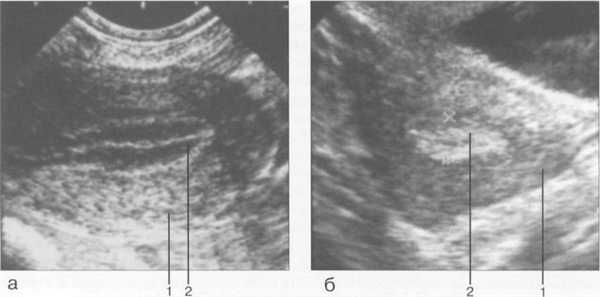

С началом пубертатного периода (от наступления менархе до 16 лет) и в подростковый период (от 16 до 18 лет) эндометрий подвержен циклическим изменениям гормонального гене-за (рис. 15.2). Обычно эндометрий имеет среднюю эхогенность, однородную структуру. Во время менструации полость матки заполнена кровью и обрывками эндометрия — в этот период на эхо-граммах М-эхо выглядит как сложная преимущественно гиперэхогенной линейной эхост-руктуры. После прекращения менструального кровотечения и освобождения полости матки от крови в первые дни после менструации М-эхо либо не определяется, либо выявляется в виде гиперэхогенной полоски толщиной 1 — 2 мм (являющейся ультразвуковым отражением соприкасающихся поверхностей функциональных слоев эндометрия передней и задней

Рис. 15.2. М-эхо у девочки 11 лет, начало пубертатного периода (трансректальное сканирование).

1 — матка; 2 — М-эхо.

стенок матки). К 5—6-му дню МЦ М-эхо представляет собой структуру в виде трех гиперэхо-генных линий: сам эндометрий, особенно в центральных отделах, является практически ан-эхогенным за счет высокой степени его гидрофильности, внутренние участки на границе с ми-ометрием имеют плотную структуру и представлены в виде двух гиперэхогенных линий, а центральная полоска представляет собой соприкасающиеся отделы передней и задней стенок матки (рис. 15.3, а; 15.4, а).

Величина М-эхо к 14-му дню МЦ (периовуляторный период) у женщин детородного периода может составлять до 14 мм. На протяжении 1 недели после овуляции эхогенность эндометрия продолжает нарастать — сначала в базальной зоне, а затем в поверхностных отделах; появляется ободок пониженной эхогенности. К 21-му дню МЦ эндометрий становится полностью гиперэхогенным (за счет накопления в клетках секрета), по периферии выявляется гипоэхоген-ная зона (обусловленная расширенными сосудами миометрия на границе с базальным отделом эндометрия) (рис. 15.3, б; 15.4, б ). Высота эндометрия остается прежней (как в 1-й фазе), но к моменту наступления менструации отмечается некоторое уменьшение его высоты.

Рис. 15.4. УЗ И, трансвагинальное сканирование.

а — М-эхо в фазе пролиферации; б — М-эхо в фазе секреции. 1 — матка; 2 — М-эхо.